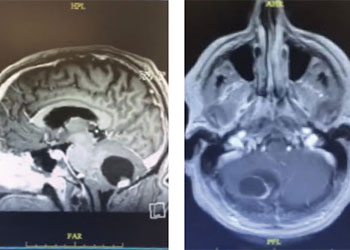

Endovascular:

Hydrocephalus and Brainstem Tumor

Author: Jonathan L. Brisman M.D., F.A.C.S., Read More!

Brain:

Pineal Region Meningioma

Author: Michael Brisman M.D., F.A.C.S., Read More!